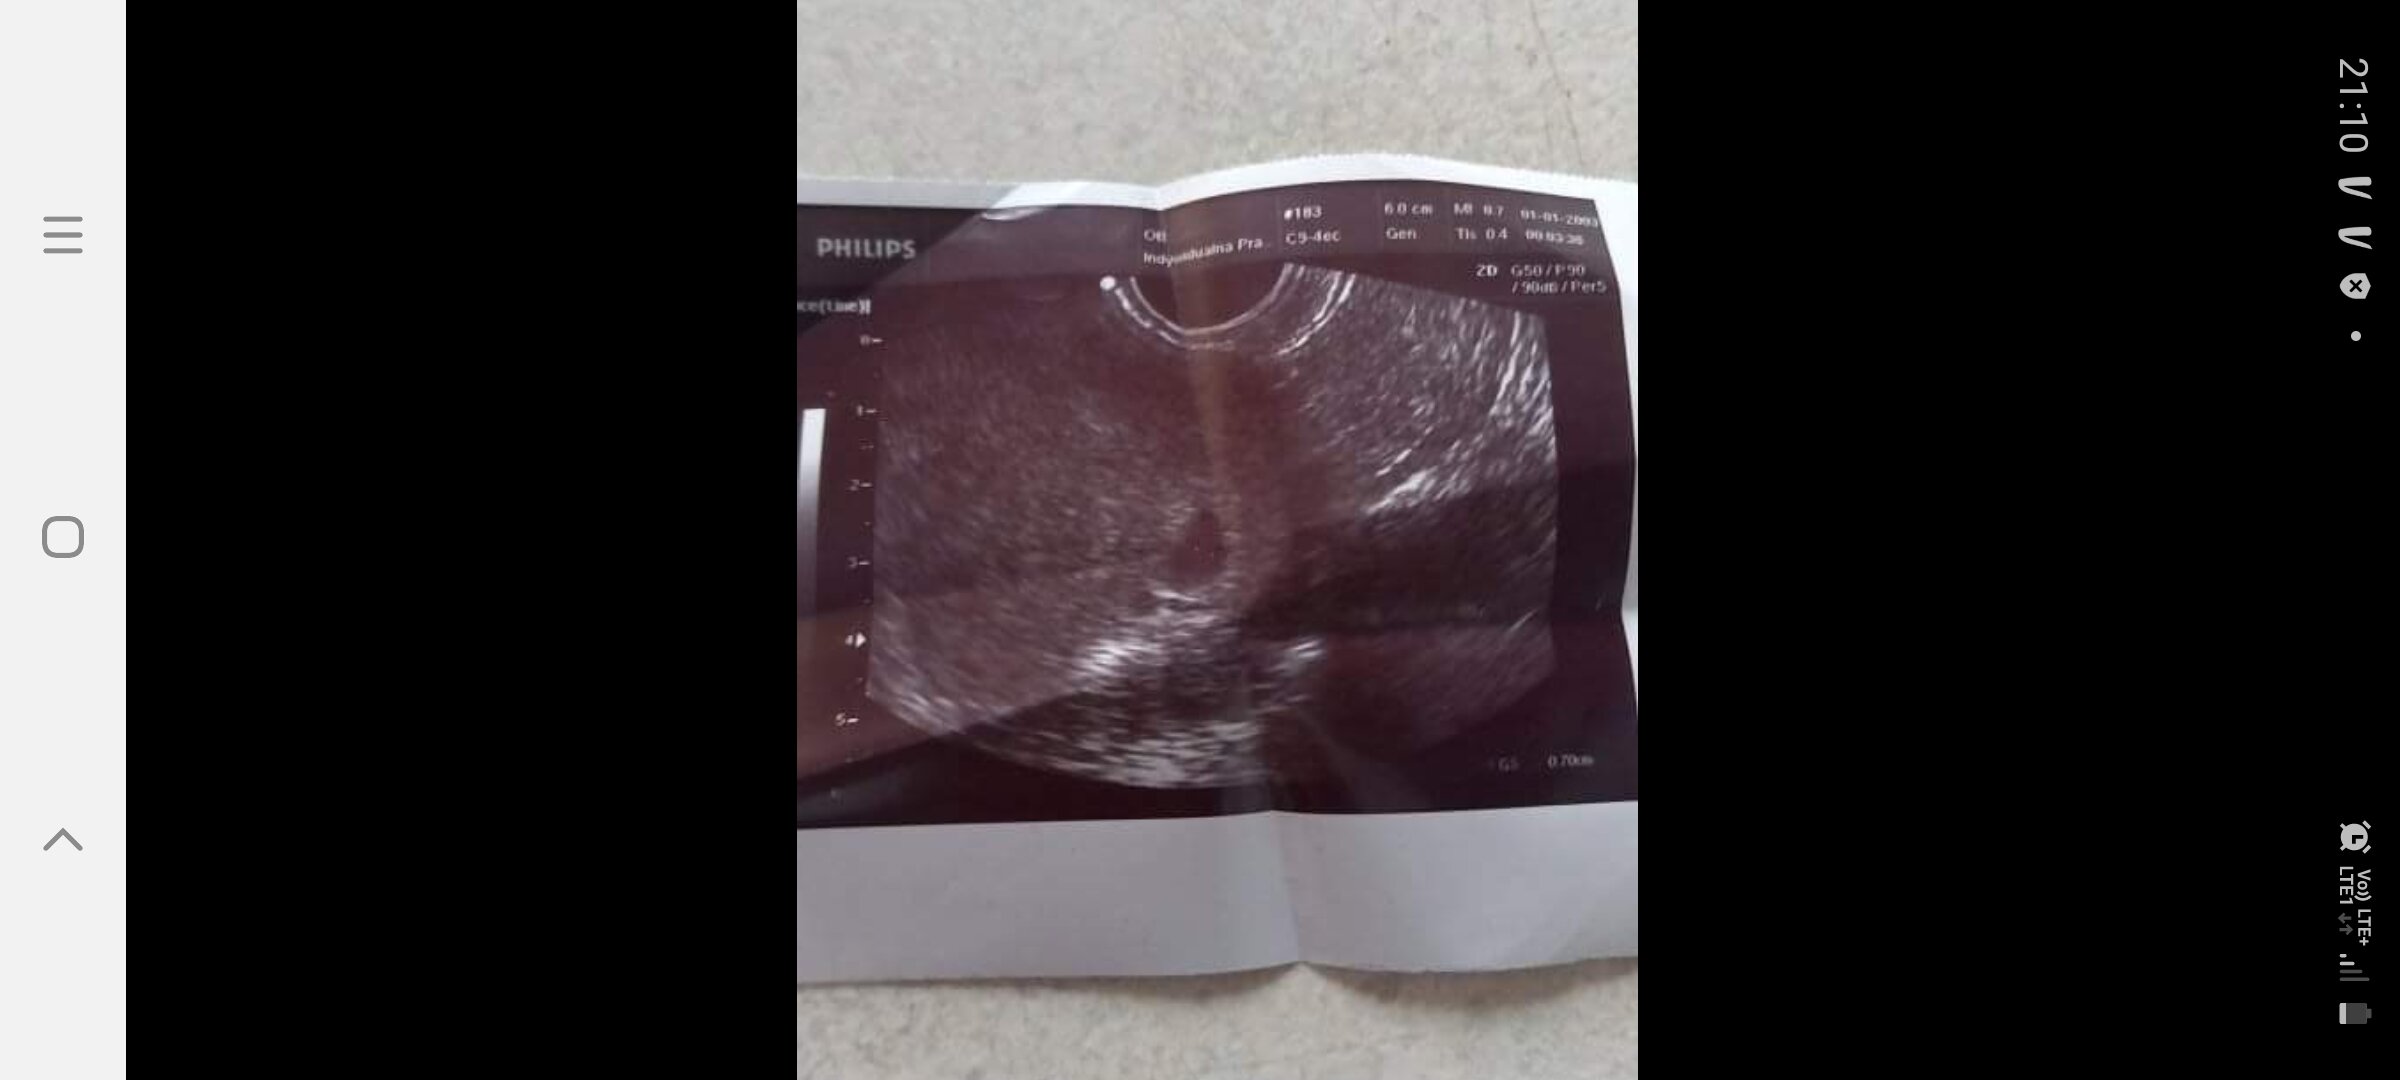

Witajcie jestem tu nowa.jak wynika z obliczeń jestem w 6 tygodniu ciąży.Dwa dni temu byłam u ginekologa który stwierdził ciąże.Jednak nie pokazał mi płodu jego badanie było szybkie i niewyraźne stwierdził że to jeszcze wcześnie i kazał przyjść za 10 dni.Bardzo się boje ponieważ naczyrałam się że w tym czasie wyraźnie powinien być zarysowany płud i bez problemu powinno być go widać nie wiem co robić czy zmienić lekarza czy czekać na następną wizytę do mojego pytania dołączam zdjęcie z usg

• Screenshot_20210730-211051_Messenger.jpg